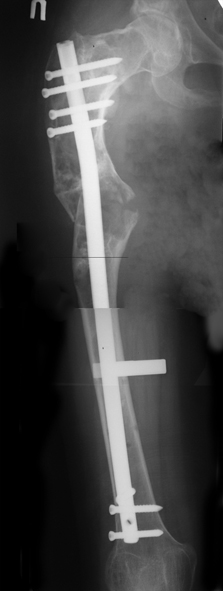

В ноябре этого года я обращался с просьбой о помощи в выборе тактики лечения больной с деформацией бедра на почве фиброзной дисплазии. Были получены интересные и очень полезные советы по операции.

Хотелось бы показать, что получилось в результате.

Операция выполнялась с помощью А.Н.Челнокова. Очень понравилась технология выполнения блокируемого остеосинтеза с использованием спицевого дистрактора, модифицированный гвоздь с латерализованным проксимальным отделом и возможностью многовинтовой фиксации проксимального и дистального участков бедра.